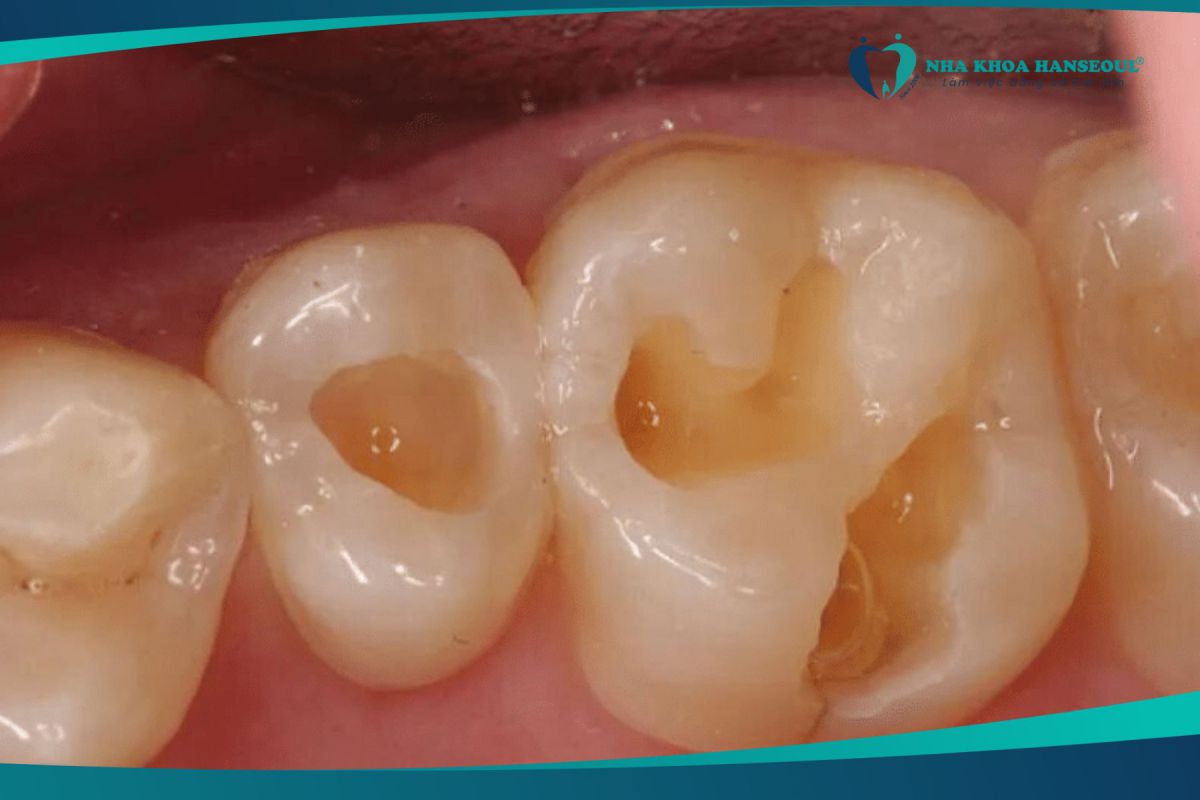

Xuất hiện những lỗ sâu trên răng

Vi khuẩn tấn công và gây ra các lỗ nhỏ trên răng hoặc tạo kẽ hở ở 2 bên răng, làm cho vụn thức ăn dễ mắc vào. Nếu không làm sạch những mảng bám này, sẽ càng tạo điều kiện cho vi khuẩn phát triển nhanh chóng hơn.

Đây là một trong những biểu hiện của bệnh sâu răng rõ ràng nhất. Bạn cần đến nha khoa để bác sĩ trám những lỗ sâu này lại trước khi vi khuẩn ăn sâu vào tuỷ răng.

Khi bị sâu răng nặng sẽ ảnh hưởng đến thẩm mỹ của bề mặt răng một cách nghiêm trọng. Dấu hiệu phổ biến khi tình trạng răng sâu đã ở mức độ nặng hơn chính là toàn bộ phần men răng bị phá hủy, lộ ra phần tủy răng bên trong làm cho cho răng bị sâu đen. Do đó, khi giao tiếp sẽ khiến người đang bị sâu răng nặng cảm thấy tự ti và mặc cảm.